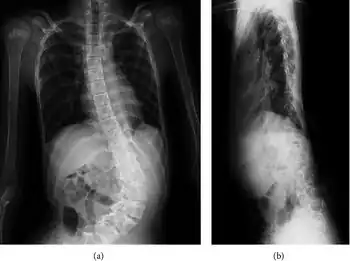

People with Shprintzen-Goldberg syndrome can experience a range of symptoms that vary in severity. Due to craniosynostosis, people with SGS may have a long and narrow head, wide spaced protruding eyes that may slant downwards, a high and narrow palate, a high and prominent forehead, a small lower jaw, and low-set posteriorly-rotated ears. Some other skeletal abnormalities people with SGS may experience include joint hypermobility, clubfoot, scoliosis, camptodactyly, arachnodactyly, long limbs, and a chest which appears to sink in or stick out. Other symptoms that may be experienced include brain abnormalities (i.e. hydrocephalus), developmental delays, intellectual disability, gastrointestinal problems (i.e. constipation, gastroparesis), abdominal or umbilical hernias, easily bruised skin, trouble breathing, and hypotonia. Some cardiac issues which are occasionally seen in people with SGS include aortic aneurysm, aortic regurgitation, aortic root dilation, mitral valve regurgitation, and mitral valve prolapse.[4]